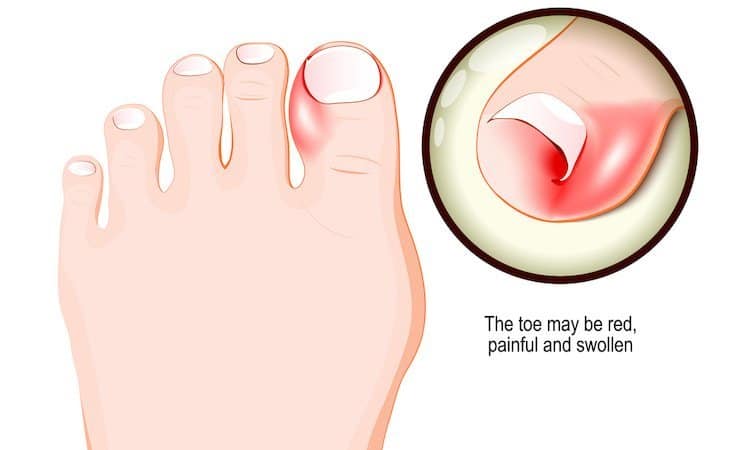

Ingrown Toenail Treatment Causes Prevention Foot Pain Explored

Ingrown Toenail Management in Singapore Straits Podiatry

Ingrown Toe Nail Removal And Treatment Doctor Chicago iL

Ingrown Toenail Treatment Brisbane The Ingrown Toenail Ctr

Ingrown Toenail Removal Treatments Ingrown Toenail Specialist